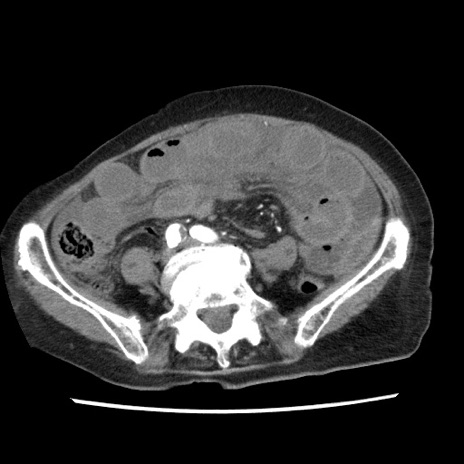

矢状断像

【症例】80歳代女性

【主訴】腹痛

【現病歴】8時間前から腹痛あり来院。

【既往歴】糖尿病、脂質異常症、子宮体癌にて子宮全摘術

【身体所見】意識清明・会話良好だが腹痛で苦悶様、全腹部にわたって反跳痛と圧痛あり

【データ】WBC 13600、CRP 0.14、LDH 224、CK 90